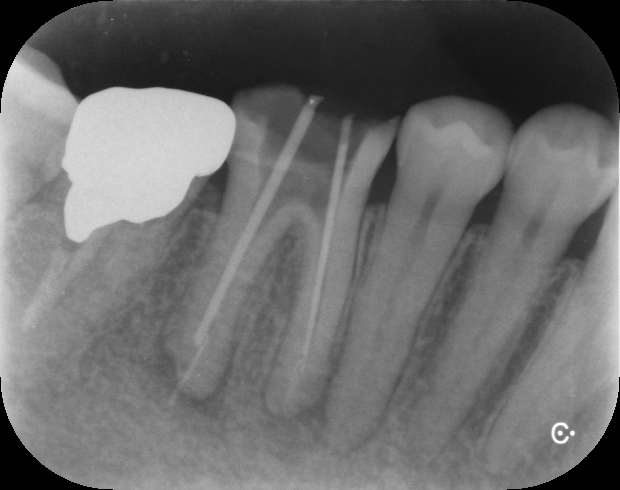

BEFORE

AFTER

治療前

治療後

半年後